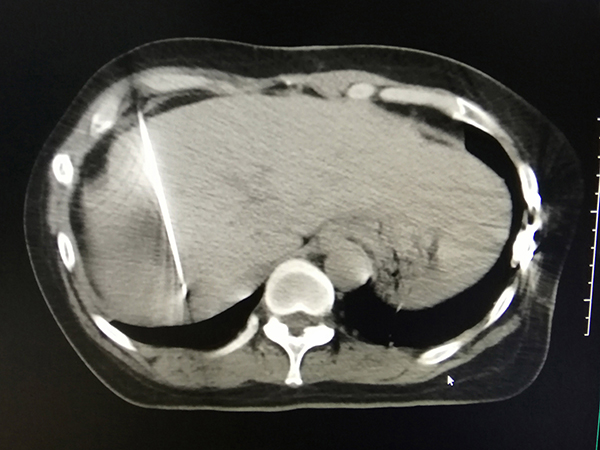

治療中